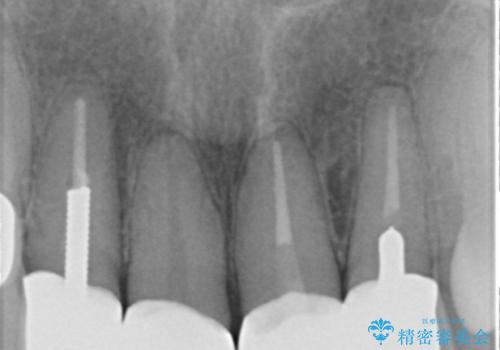

- 前歯の詰め物が頻繁に外れるとのことで来院。

これを機にセラミックでかぶせて、前歯の歯並びも良くしたいとのことでした。

左上の前歯のみねじれが大きいため、歯の位置をひっこめたかぶせものにするために、神経の治療を行っています。

両側の前歯もやり替えをすることで、前歯の前突感も無くしています。

両側の歯の神経の治療および土台のやり替えは行っていません。